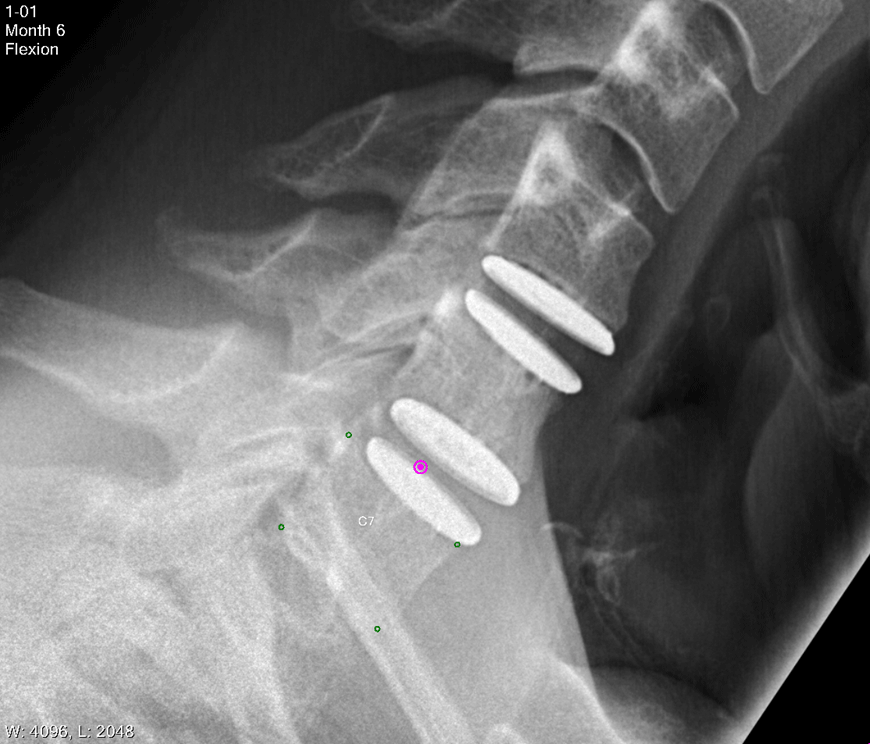

The Freedom® Lumbar Disc (FLD) and Freedom® Cervical Disc (FCD) are intended to replace degenerated lumbar or cervical discs, with polymer cores designed to provide the kind of stiffness similar to that found in healthy human discs. Like human discs, the cores are viscoelastic, which means they respond to different loads and loading rates the way a human spine does.